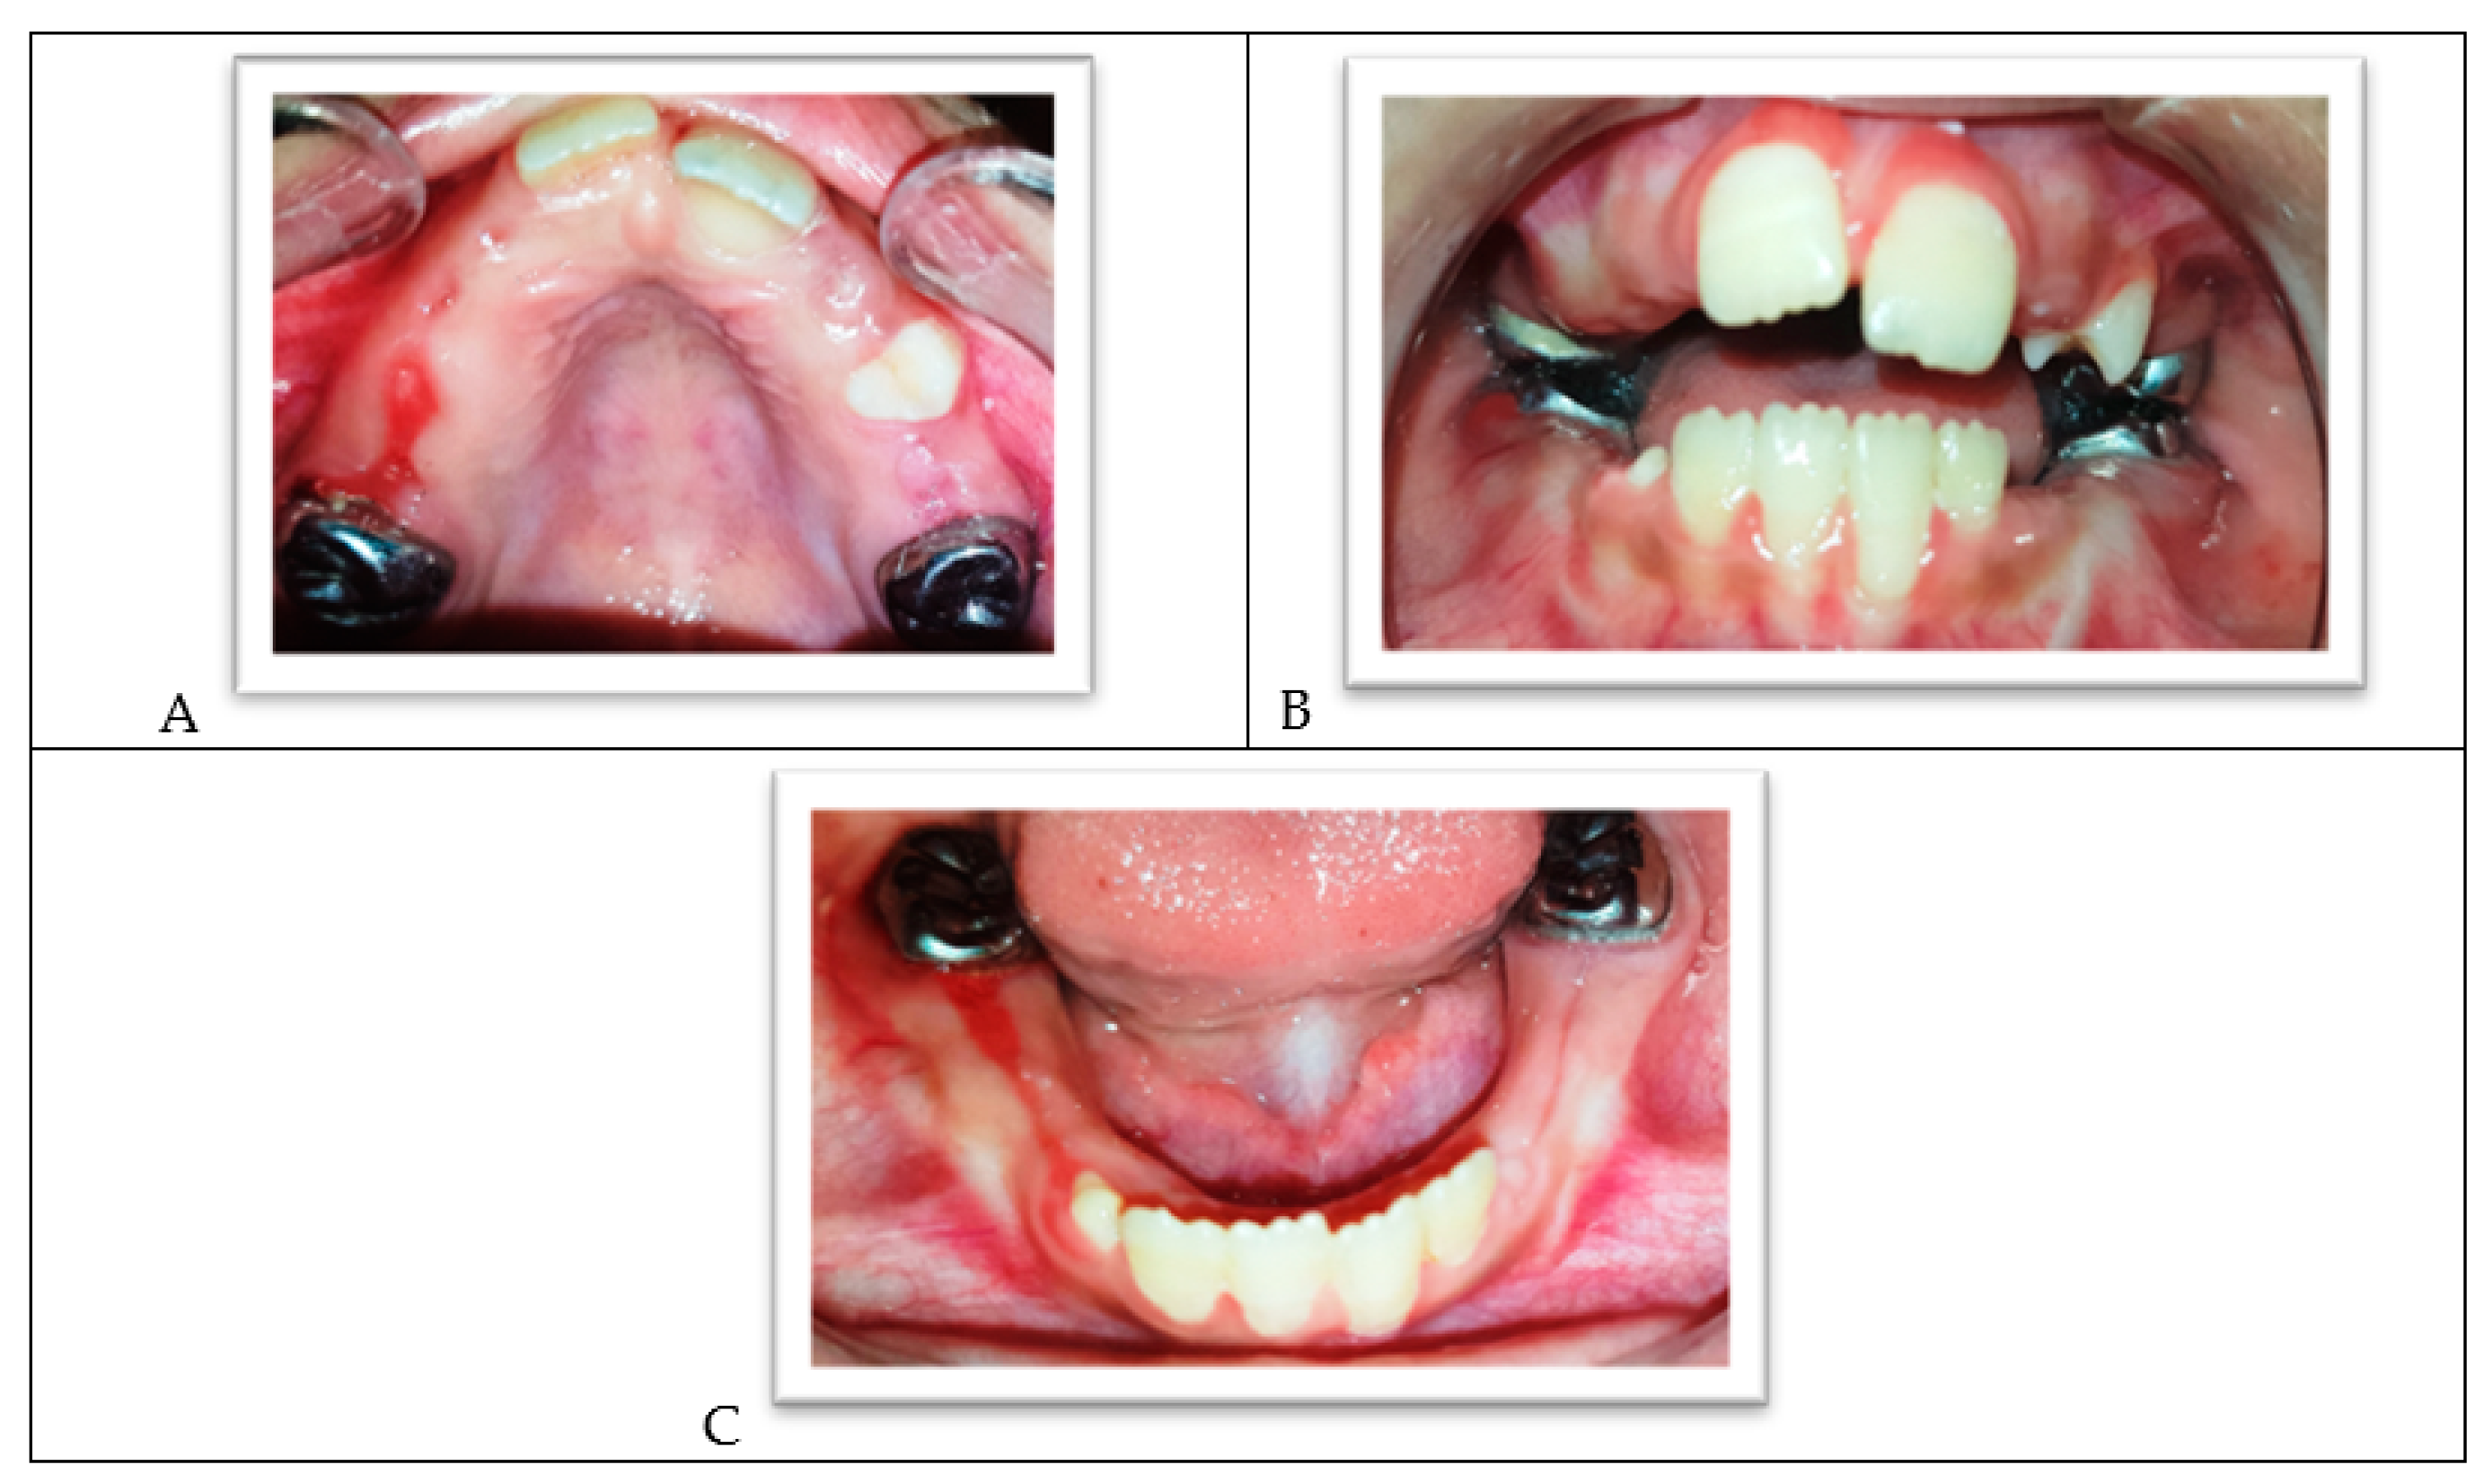

The intraoral clinical examination showed generalized gingivitis, dental plaque accumulation, and a mild gingival enlargement in the anterior area. Many permanent and primary teeth showed extensive carious lesions. The upper-left central incisor presented signs of hypomineralization and decalcification in the sense of an initial carious lesion (Figure 2A–C). The child was in the transitional dentition with class I molar relationships, showing a mild crowding in lower incisors and a dentoalveolar anterior open bite. The child’s thumb sucking and tongue thrusting habits might have contributed to her malocclusion. The lower primary molars were treated three years ago, but the dental history showed that the child lacked the cooperation ability to complete the treatment correctly (Figure 2C).

Figure 2.

(A) The upper arch. (B) Frontal view of both arches in occlusion. (C) The lower arch.